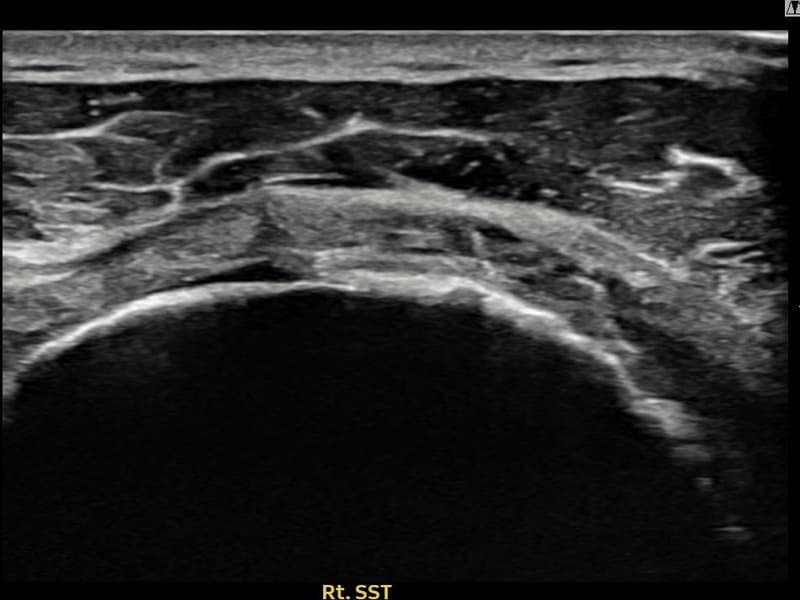

After

시술 전 초음파 측정 결과 파열 크기는 16mm × 5mm (힘줄 두께의 약 75% 결손)로 확인되었습니다. 시술 전 초음파에서 우측 극상근건 관절면측의 광범위한 에코 단절과 힘줄 두께의 심각한 감소가 확인되었습니다. 시술 후 초음파에서 광범위 파열 부위에 재생 조직이 형성되고 힘줄 연속성이 안정적으로 회복된 것이 관찰되었습니다.

60대 초반 남성 환자분으로, 타 병원 두 곳에서 전층파열 직전 단계라며 수술을 권유받으셨으나 수술 후 재활 기간과 합병증 위험 때문에 비수술 치료를 원해 내원하셨습니다. 정밀 초음파 검사에서 관절면측 극상근건의 광범위한 부분파열이 확인되었으며, 힘줄 두께가 건측 대비 75% 이상 감소된 상태였습니다. 파열 범위가 넓어 일반적인 주사 치료나 물리치료로는 구조적 회복이 어렵다고 판단하였으며, 초음파 유도 하 축소봉합술을 시행하였습니다. 시술 후 보조기 착용 6주를 유지하며 단계적 재활을 진행하였고, 11주 후 추적 초음파에서 재생 조직 형성과 힘줄 연속성 회복이 확인되어 수술 없이 안정적인 치료 결과를 얻으셨습니다.